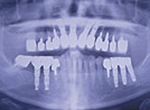

パノラマレントゲン